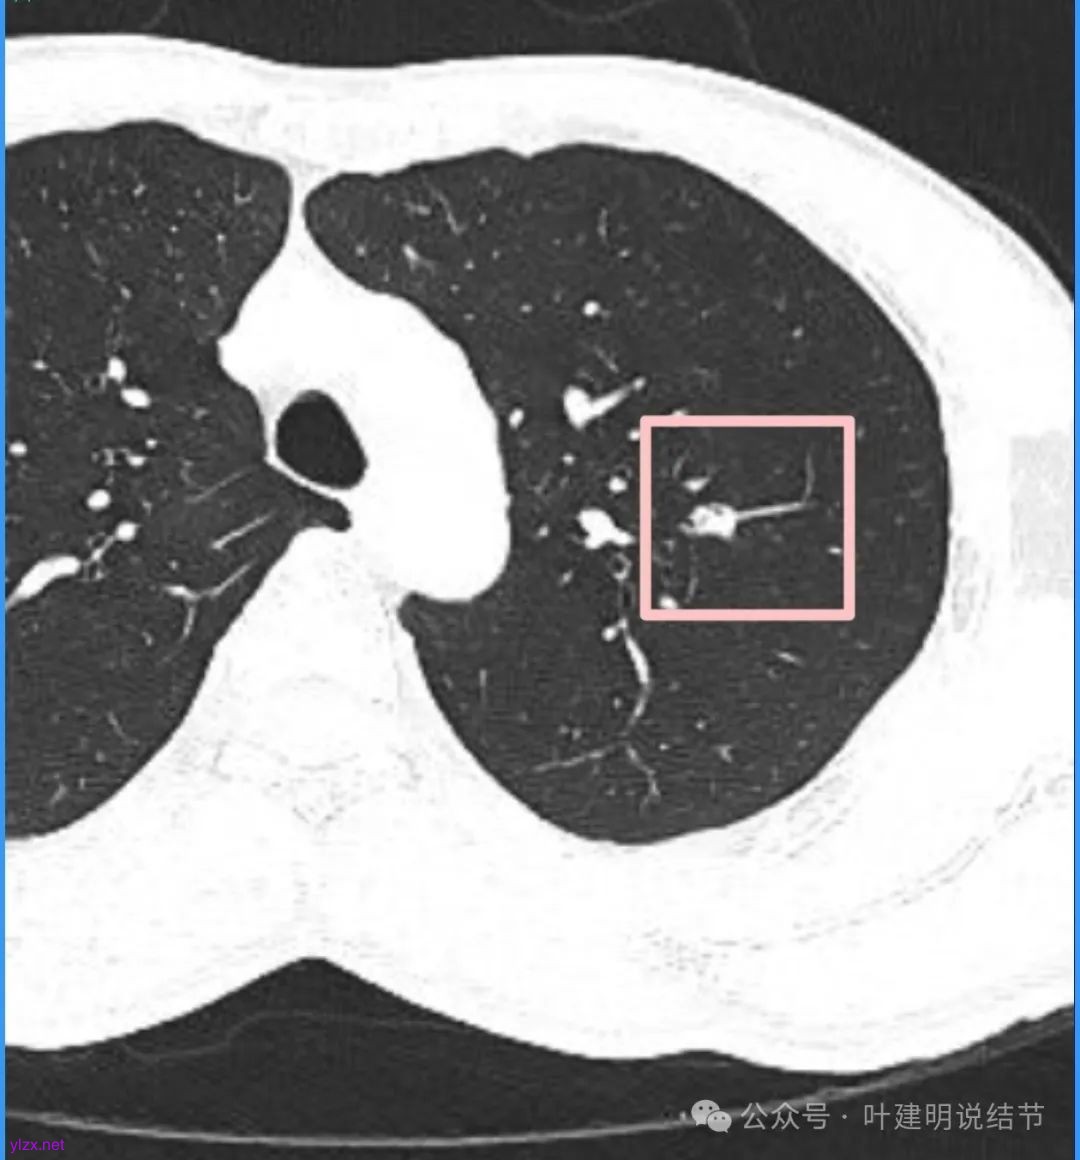

我们先来看2025年3月时的影像:

病灶密度不均,混合密度的样子,相应的细支气管有扭曲略显扩张。

边缘较为毛糙不平,灶内密度杂乱,细支气管穿行,整体轮廓较清。

邻近血管受结节影响,略向病灶侧弯,病灶处是扩张的细支气管还是灶内的空泡征?

有血管征,整体轮廓与边界较清,灶内有蜂窝状。

血管穿过病灶,灶内多个小空泡,整体轮廓较清。

蓝色部分似乎是血管,但似乎又是增厚的支气管壁,局部细支气管扩张。

特别上上图边缘些的层面,蓝色箭头所指的实性明显又像位于扩张细支气管内或与支气管壁一块的样子。